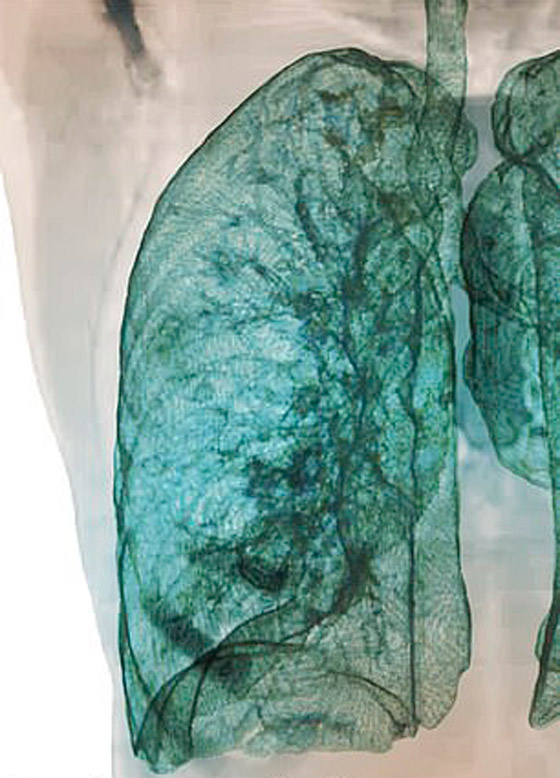

تصوير مقطعي محوسب من مستشفى جامعة جورج واشنطن يُظهر آثار فيروس كورونا المستجد، أو ما يُعرف بـ"كوفيد-19" رئتي رجل عمره 59 عاماً. فشاهدوا معنا في الفيديو المدهش أدناه كيف تبدو رئة مصاب بفيروس كورونا (فيروس كوفيد 19) وما يحصل داخلها..